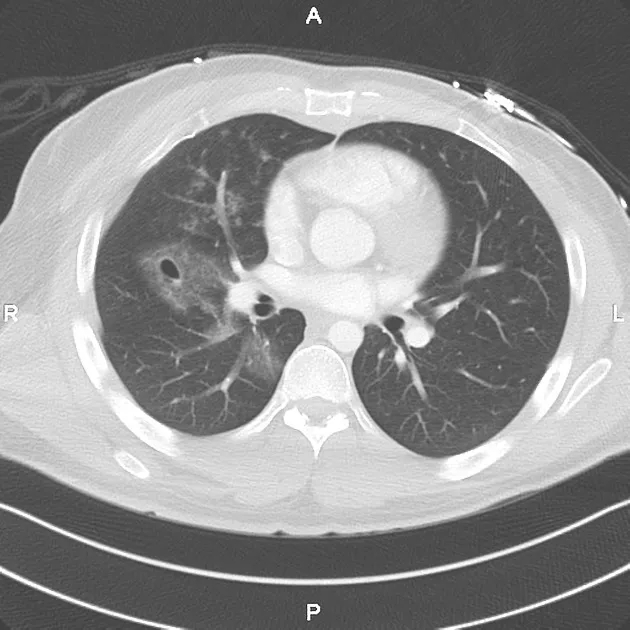

创伤性假性肺囊肿依据囊肿内血液及气体的多少分为 3 型:空腔型、囊肿型、气-液囊肿型(混合型);

单纯充满气体者称为空腔型;

3587a976830c68733d78ba4c6b7f4d72.jpg

创伤性假性肺囊肿多分布在肺野外周,可以伴骨折、肺挫伤、液气胸及纵隔、皮下气肿同时出现,囊肿内壁均匀、光滑,边缘多有斑片状渗出呈磨玻璃影或实变影改变,边界不清;短期内复查囊肿内密度容易变化,可以出现 3 种类型囊肿相互之间转化,但以空腔型转化为气液型囊肿或囊肿型转化为气液型囊肿较为多见

诊断创伤性假性肺囊肿需要有明确的外伤史此疾病多处于肺挫伤附近或中心,病变不稳定,短时间内病灶大小、形态均有明显改变。